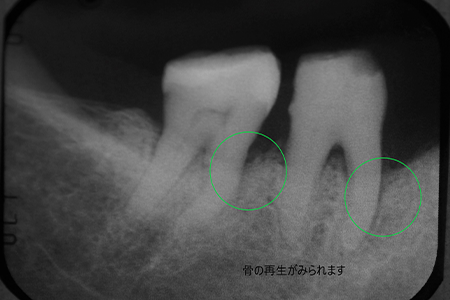

| 治療の経緯 | 口臭と歯が揺れているとのことで来院された患者様です。 歯周ポケットが10mmあり、歯茎も腫れ、このままただのクリーニングだけだと数年後には確実に抜歯になることが予想されます。 |

| 治療方法 | 再生療法を行い、骨の再生を促しました。 レントゲンを見る限り、明らかな骨の再生が見受けられます。 |

| 治療期間 | 12ヵ月 |

|---|---|

| 費用 | 再生療法 7万円 クリーニング 1万2千円/毎月×12ヵ月 |